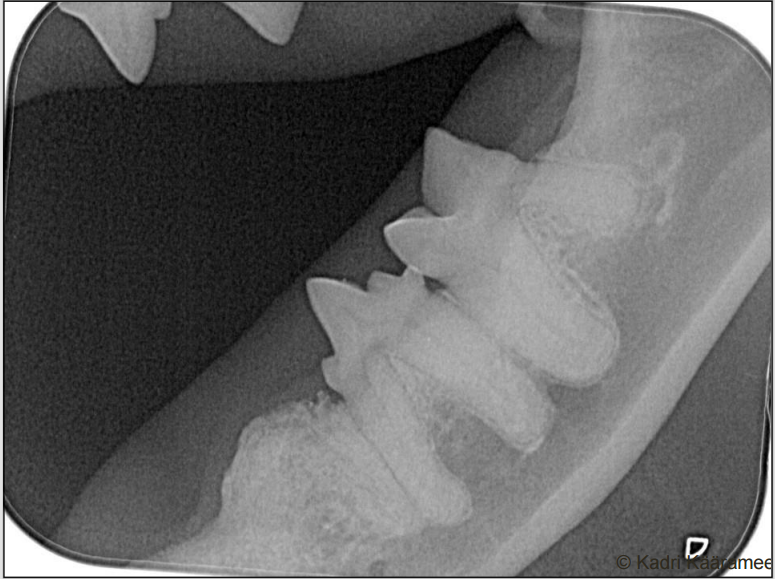

tooth resorption lesion that has reached the crown and granulation tissue as formed a strawberry red uloke

How well did you know this?